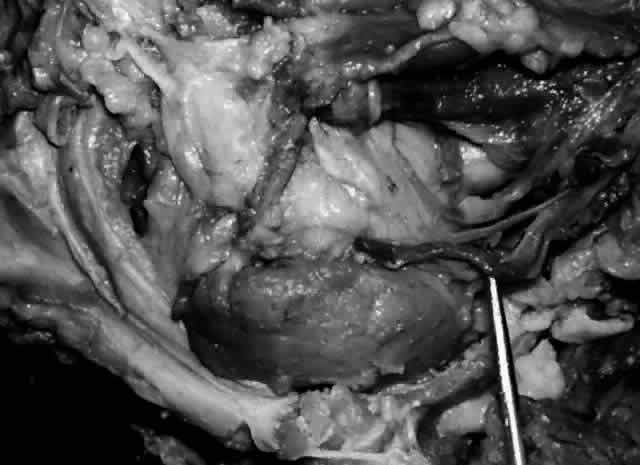

These attachments may become attenuated in older persons, allowing the gland to herniate through a weakened orbital septum to give a temporal bulge in the upper eyelid (Fig. 3). The lacrimal gland tissue is usually grayer and pinker than the surrounding yellow adipose tissue.

The almond-shaped orbital lobe (see Fig. 2) represents approximately 65% to 75% of the gland and measures 20 mm long × 5 mm thick × 12 mm wide.2 Its sharp anterior border rests behind the superior orbital rim and is covered by the orbital septum (Fig. 4) and a portion of the temporal aspect of the central preaponeurotic fat pad (Fig. 5). Posteriorly, its rounded border is supported by a large superotemporal fat pad at the plane of the posterior pole of the globe.3 The convex superior surface is suspended from the periorbita of the lacrimal gland fossa of the frontal bone. The inferior border is convex and attached to the sheath of the levator aponeurosis. Its lateral border is smooth and convex in contour with the bony fossa.